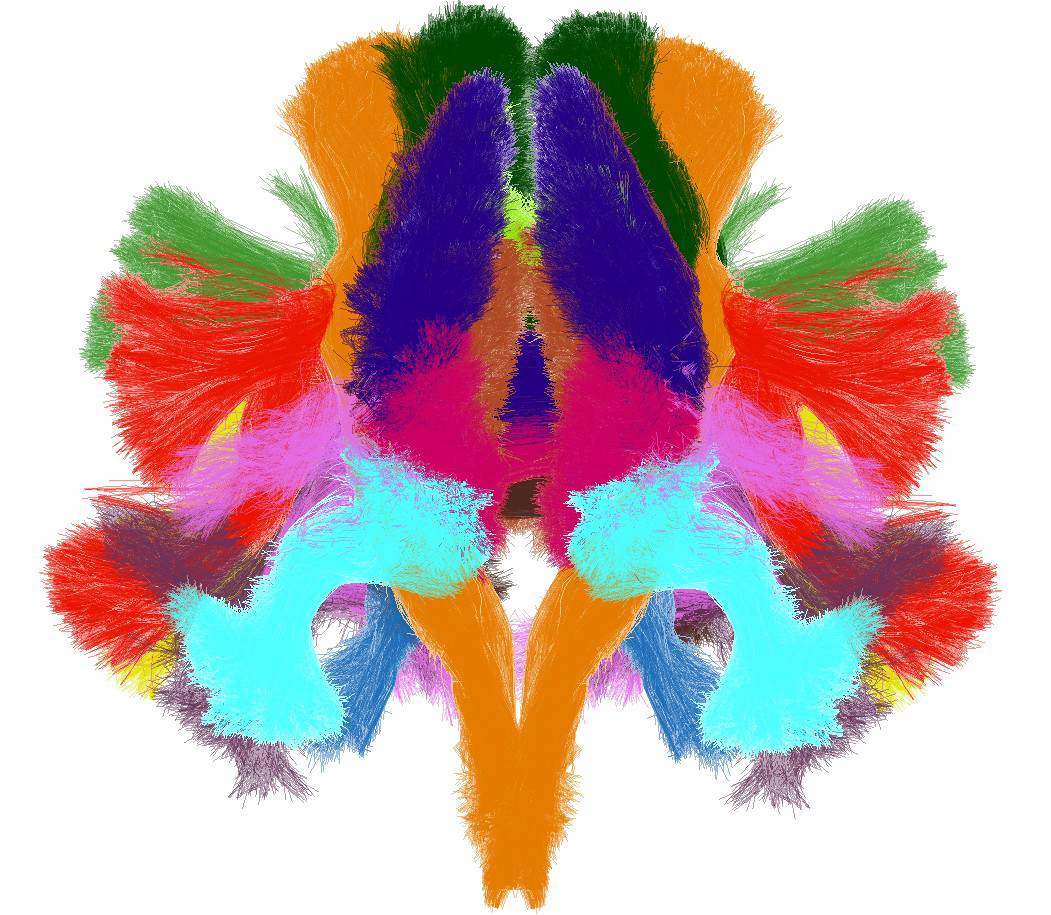

In this context, it develop the “Connectomist” software platform integrating all the needed steps to study the connectome structure and it has also published the first human brain anatomic atlas displayed on the next Figure.

Beyond the angular profile of water molecule displacement, dMRI allows to probe the biological tissues at the cell scale, because throughout its microscopic movements, the water molecules bump into cell walls (glial, neuronal, axonal, astrocytic…) and therefore encode membrane geometry of these cells. All the work of the biophysicist is to « decode » this information and modelling the different brain tissues with this help of simple mathematical templates of the membrane geometry. At the end of the first decade of the 21st century, this new modality is on his way to transform MRI into a fantastic virtual biopsy tool allowing a none-invasive exploration of the tissue organization at the cell scale: it is called microscopy by diffusion MRI or μdMRI. NeuroSpin has made the methodological MRI developments which enable it to offer to its platform customers the microscopy diffusion MRI sequences (Lebois et al, 2012) in addition to the associated analysis tools that we have shown the forcefulness building the first quantitative atlas of the large bundles of the white matter, as illustrated on Figure 4 (Assaf et al, 2013 ; Duclap et al, 2013 , Schmitt et al, 2012).